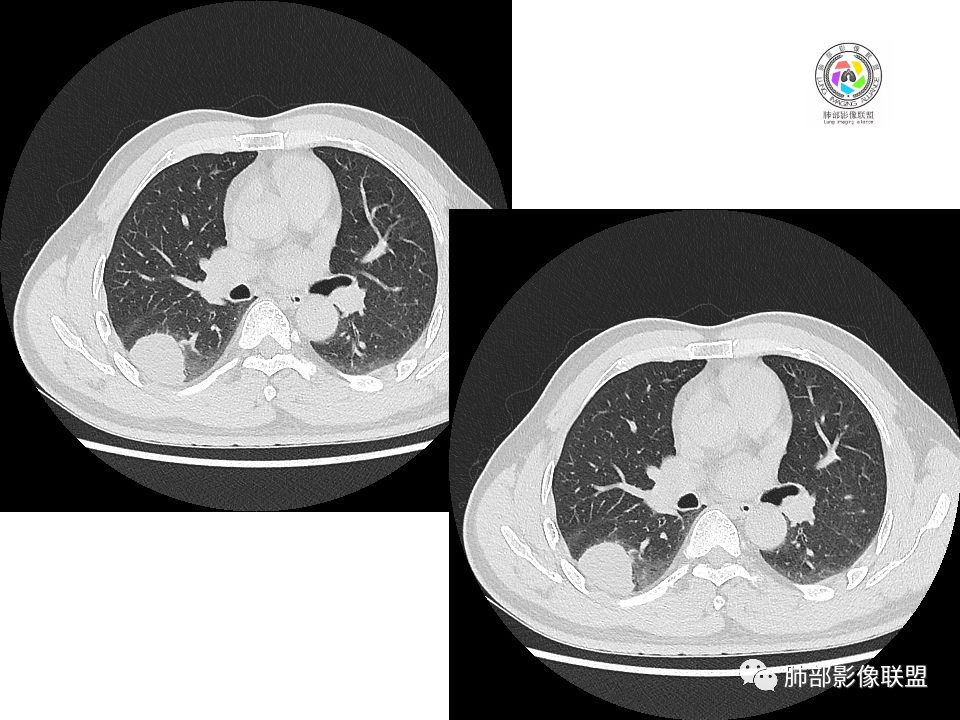

右肺下叶背段胸膜下见团块影,边缘清,其后基底段见一扁平状结节,各见‘’平直及桃尖"征,均轻度强化,右肺上叶背段及中叶外侧段分别少许纤维化灶及部分卫星病灶,一元考虑TB,与隐球菌鉴别!

右肺下叶胸膜下类圆形团块,边缘光滑无毛刺分叶,强化均匀无坏死,另血管旁小结节平直桃尖,上叶小斑片影,考虑结核或者真菌感染。

右肺下叶背段胸膜下见一边缘稍模糊、浅分叶结节灶,密度均匀,似乎轻度均匀强化(具体CT值看不出来),与胸膜锐角相贴,似有平直征和桃尖征。此病灶前内侧还有类似小结节,轻度强化,右肺上叶后段有斑片状稍高密度影:考虑良性病变,炎性结节可能。

晨读,右肺下叶背段胸膜下见肿块影,边缘清晰,未见与气管相连通,右下叶见结节影边缘清晰,两处病变密度均匀,同步不明显强化,中叶外侧段斑点状影,树芽征,考虑1良性病变,结核?隐球菌?2淋巴瘤待除外。

右肺下叶背段胸膜下宽基底团块状占位,浅分叶,边界清晰,胸膜下脂肪间隙清晰,背段支气管管壁似乎增厚,未见明显强化。外侧基底段血管束间结节,边界清晰,亦未见明显强化。中叶外侧段见少许树芽征象。纵隔未见明显肿大淋巴结。我先猜个结核。

男性,49岁,体检发现,右肺下叶背段胸膜下见肿块,边界清楚,边缘光滑,胸膜下脂肪间隙存在,有分叶,无毛刺,均匀强化,内无坏死,右肺下叶血管束间不规则实性结节,边界清楚,无明显强化,中叶少许斑片状高密度影,纵隔未见明显增大淋巴结,考虑良性病变。

右下肺占位并淋巴结肿大,边缘光滑,强化不明显,指状突起。考虑恶性肿瘤,不除外小细胞,鉴别诊断肺结核。

中年男性,体检发现病灶,右肺下叶背段胸膜下见团块影,边缘清晰,与气管关系不密切,右肺下叶见一小结节影,边缘清晰,两处病变密度均匀,增强病灶强化不明显,偏向良性病变,隐球菌?炎性假瘤?

右肺下叶肿块,边界清楚,边缘有晕,光滑,无毛刺,均匀强化,无坏死,中叶少许斑片状高密度影,粘液栓,考虑良性病变,隐球,鉴别结核。

中年男性,有吸烟史,右肺下叶靠近胸膜下类圆形肿块,边缘光滑,有膨隆,浅分叶,周围有磨玻璃影,附近有血管进入,与支气管关系不大,宽基底与胸膜相连,胸膜增厚不明显,密度均匀,轻度强化;右肺下叶近端有一不规则结节,有血管贴边征,右肺中叶外侧段斑片影。右肺下叶靠近胸膜下肿块考虑恶性神经内分泌肿瘤,大细胞肺癌可能性大。靠近肺门端结节考虑转移?右肺中叶炎症。鉴别隐球菌肺炎。

中年男性,无症状,右肺下叶背段团块影,边缘清晰,周围晕征,增强病灶强化不明显,考虑隐球菌。

右肺下叶二个大小结节,胸膜下结节浅分叶,指状突起,轻度强化,较小结节血管漂浮,考虑小细胞癌,类癌,鉴别隐球菌。

右肺多发结节,较大位于胸膜下,宽基底与胸膜相连,边缘光滑,分叶不明显,局部周围似有模糊GGO,支气管显示不佳,平扫密度均匀,增强后强化不明显,考虑良性,IMT,隐球菌,鉴别小细胞癌。

右肺下叶胸膜下肿块影,边界清晰,无明显分叶及毛刺,无晕征,未见明显卫星病灶,内无钙化,增强后均匀强化,未见明显坏死,近肺门侧小肿块,与血管无关,需要连续层面看与支气管的关系,无关就是淋巴道,考虑小细胞癌有可能,近肺门是淋巴转移途径?

体检发现右肺下叶胸膜下类圆形肿块,边界清晰,有膨胀感,胸膜下脂肪间隙清晰,密度均匀,增强轻度均匀强化。另右肺下叶血管束间可见一小结节影,与胸膜下大结节类似。考虑为良性病变。

中年男性,体检发现,有吸烟史。影像见右肺多个结节、肿块影,大者位于背段,靠近胸膜下类圆形肿块,密度较均匀,边缘光滑,有膨隆,浅分叶,周围有磨玻璃影,有血管进入,似与支气管关系不大,宽基底与胸膜相连、扶墙,轻度强化;纵隔内无明显肿大淋巴结。首先考虑炎性隐球菌可能,需鉴别:肿瘤病变转移。

哦落花时节

毛勤香

中年男性,体检发现占位。右肺下叶背段胸膜下肿块,周围晕征,有小分叶,与支气管、肺内血管关系不清,形似山丘,重建可见肿块呈D字形凸向肺部。似跨斜裂,似有小凸起与肋下缘相连,增强似有轻微均匀强化。右肺下叶外基底段小结节,位于血管周围,部分边缘平直,轻微均匀强化。考虑二元:一、右下叶背段肿块为肺外病变,神经鞘瘤?SFT?鉴别小细胞癌、隐球菌病;二、右下叶外基底段结节考虑为良性结节、炎性肉芽肿?

2.右肺下叶背段胸膜下块影,边界清楚光整,上下极见磨玻璃晕,未见明显分叶毛刺和棘状突起,未见胸膜凹陷或胸壁侵入。密度均匀,轻度不均匀强化。未见支气管进入。

3.右肺中叶外侧段胸膜下散在小片影,磨玻璃密度为主,边界不清,支气管相关。符合炎性特征!

4.右肺下叶基底段支气管血管束旁小结节影,边界清楚,强化不明显。注意,这结节在“遥远的”基底段。